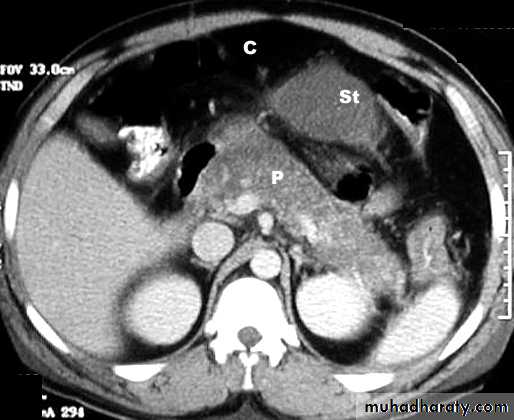

Radiology of acute pancreatitis

GIT

U/S 

useful for biliary pathology, 70-80% sensitive for pancreatitis

CT more useful for judging severity and regional effects

Try to wait >12 hours as early CT is usually unhelpful